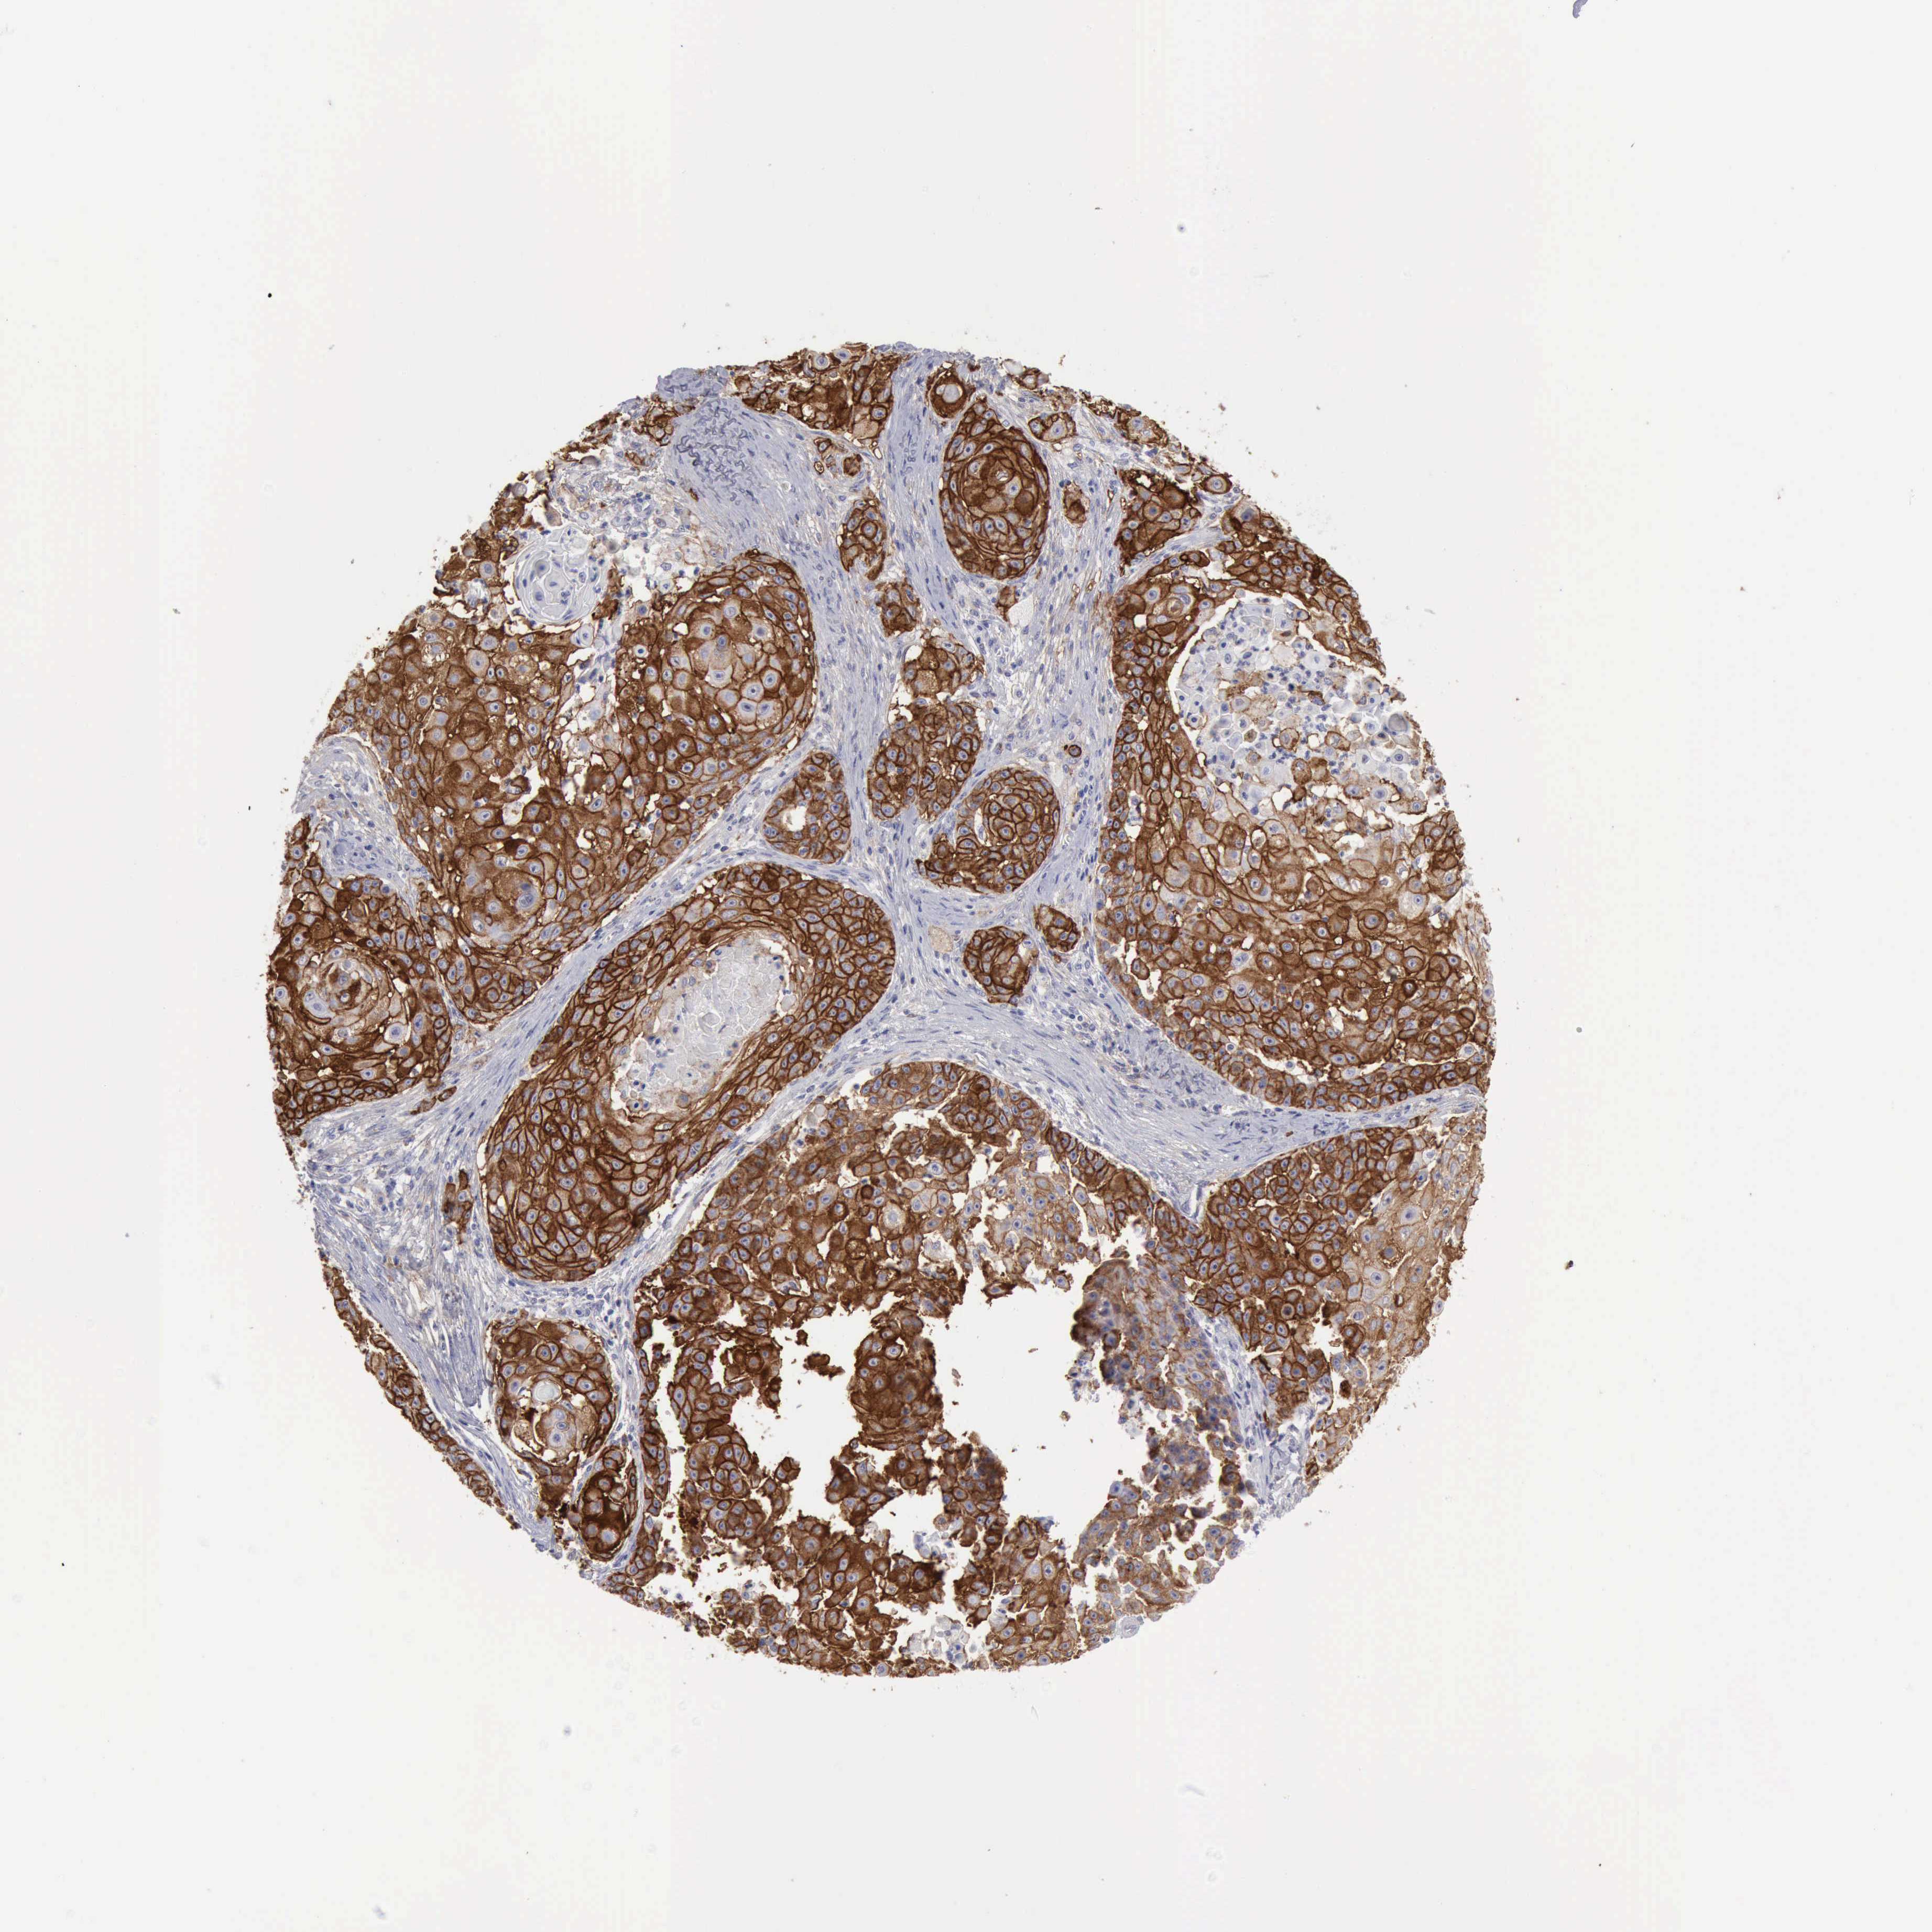

Basal cell and squamous cell cancer

SKIN CANCER - Protein expressioni

A mouse-over function shows sample information and annotation data. Click on an image to view it in a full screen mode. Samples can be filtered based on level of antibody staining by selecting one or several of the following categories: high, medium, low and not detected. The assay and annotation is described here.

Antibody staining in the annotated cell types in the current human tissue is reported as not detected, low, medium, or high, based on conventional immunohistochemistry profiling in selected tissues. This score is based on the combination of the staining intensity and fraction of stained cells.

Each image is clickable and will lead to virtual microscopy that enables deeper exploration of all samples and also displays staining intensity scores, fraction scores and subcellular localization as well as patient and tissue information for each sample.

Antibody HPA028598

Antibody CAB000153

Basal cell carcinoma

Squamous cell carcinoma, NOS

Squamous cell carcinoma, metastatic, NOS